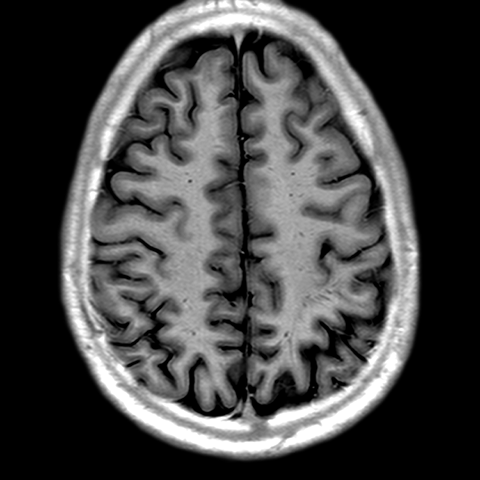

Cerebral Hemispheres, MR (normal) [1 of 9]